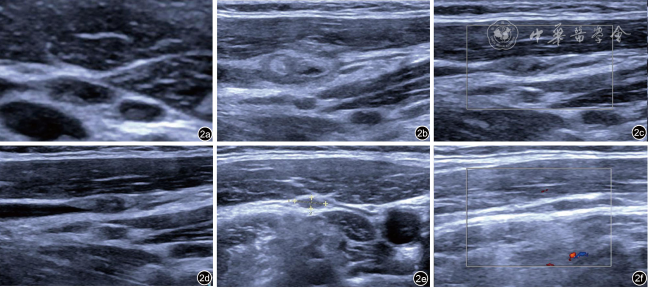

图2 甲状腺乳头状癌复发性颈部转移性淋巴结消融术前、术后超声图像。图a为术前颈部转移性淋巴结;图b为消融术后1个月复查图,可见混合不均匀回声区,以高回声为主,范围较原有淋巴结稍大;图c为术后3个月复查图,可见混合不均匀稍高回声区较前次复查缩小;图d为术后6个月复查图,与前次复查相仿;图e为术后12个月复查图,稍高回声区较前次复查缩小;图f为术后18个月复查图,原稍高回声区几乎显示不清,考虑消融灶几乎完全吸收 |